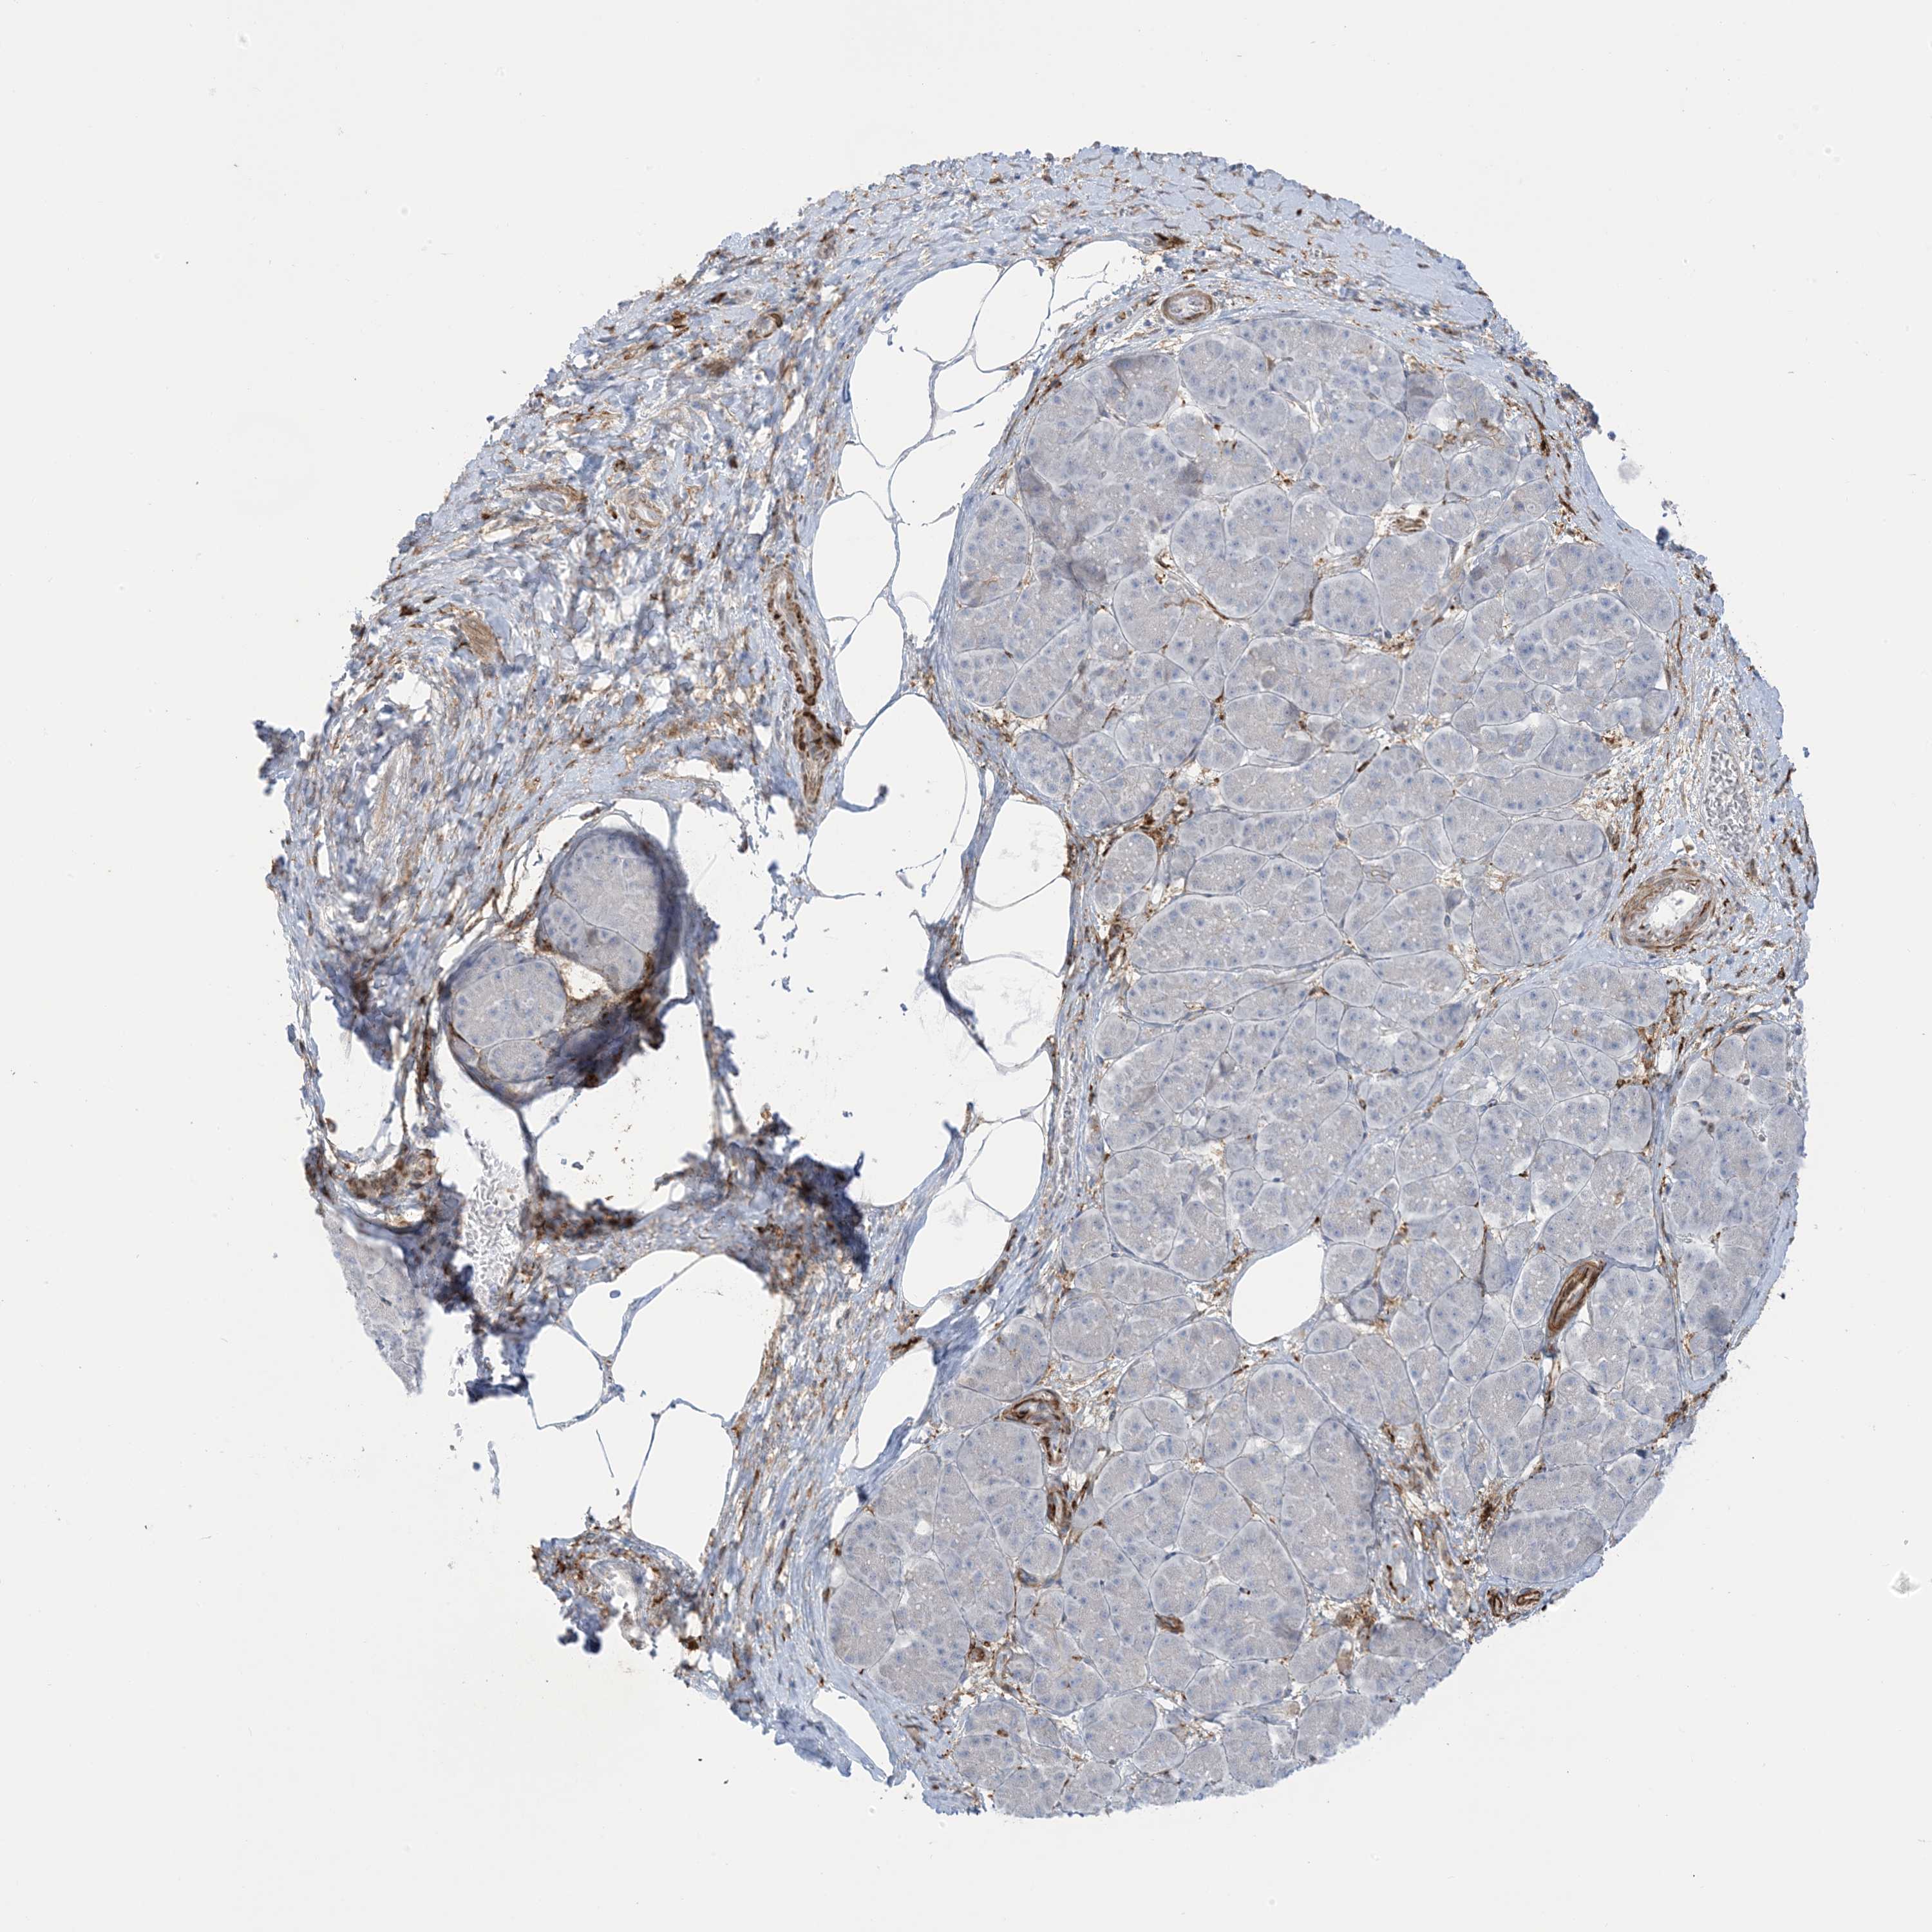

PANCREATIC CANCER - Protein expressioni

A mouse-over function shows sample information and annotation data. Click on an image to view it in a full screen mode. Samples can be filtered based on level of antibody staining by selecting one or several of the following categories: high, medium, low and not detected. The assay and annotation is described here.

Note that samples used for immunohistochemistry by the Human Protein Atlas do not correspond to samples in the TCGA dataset.

Antibody stainingi

Antibody staining in the annotated cell types in the current human tissue is reported as not detected, low, medium, or high, based on conventional immunohistochemistry profiling in selected tissues. This score is based on the combination of the staining intensity and fraction of stained cells.

Each image is clickable and will lead to virtual microscopy that enables deeper exploration of all samples and also displays staining intensity scores, fraction scores and subcellular localization as well as patient and tissue information for each sample.

Antibody HPA032024

Antibody HPA032025

Staining

High

Medium

Low

Not detected

Intensity

Strong

Moderate

Weak

Negative

Quantity

>75%

75%-25%

<25%

None

Location

Nuclear

Cytoplasmic/membranous

Cytoplasmic/membranous,nuclear

Adenocarcinoma, NOS